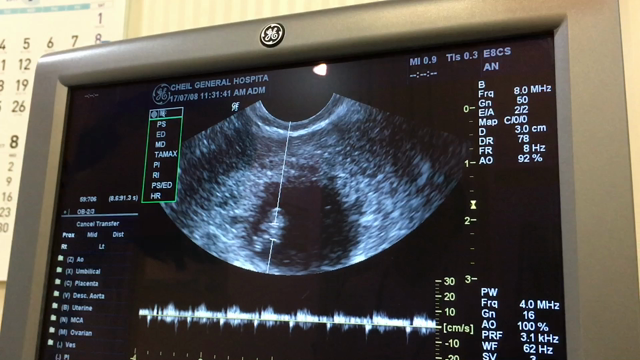

1回目の血液検査とエコー検査

出張後の検診~9w5d~

出産予定日確定